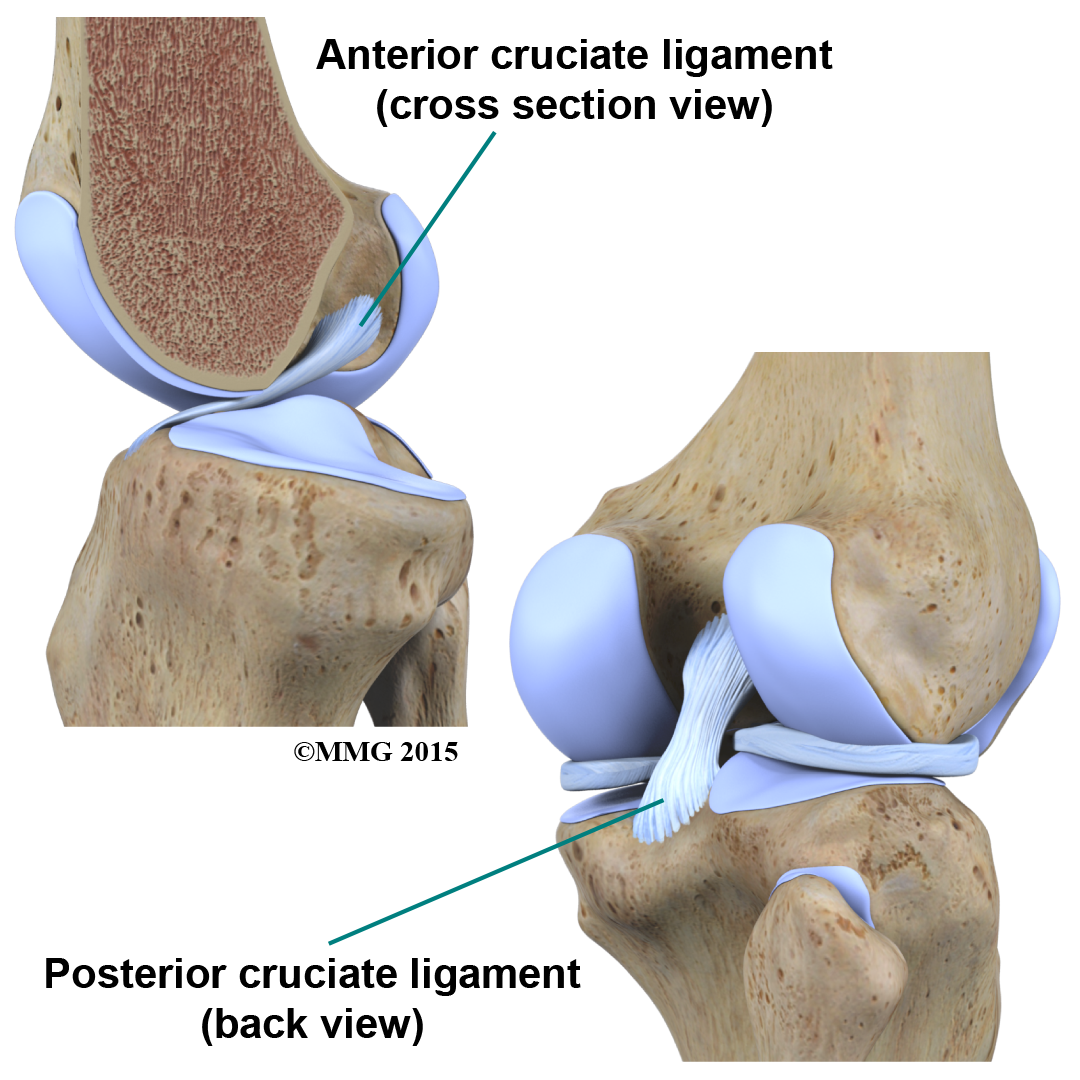

Inside the knee joint, stretch between the femur and the tibia: the anterior cruciate ligament (ACL) in front, and the posterior cruciate ligament (PCL) in back.

The MCL and LCL prevent the knee from moving too far in the side-to-side direction. The ACL and PCL control the front-to-back motion of the knee joint.

The ACL keeps the tibia from sliding too far forward in relation to the femur. The PCL keeps the tibia from sliding too far backward in relation to the femur. Working together, the two cruciate ligaments control the back-and-forth motion of the knee. The ligaments, all taken together, are the most important structures controlling stability of the knee.